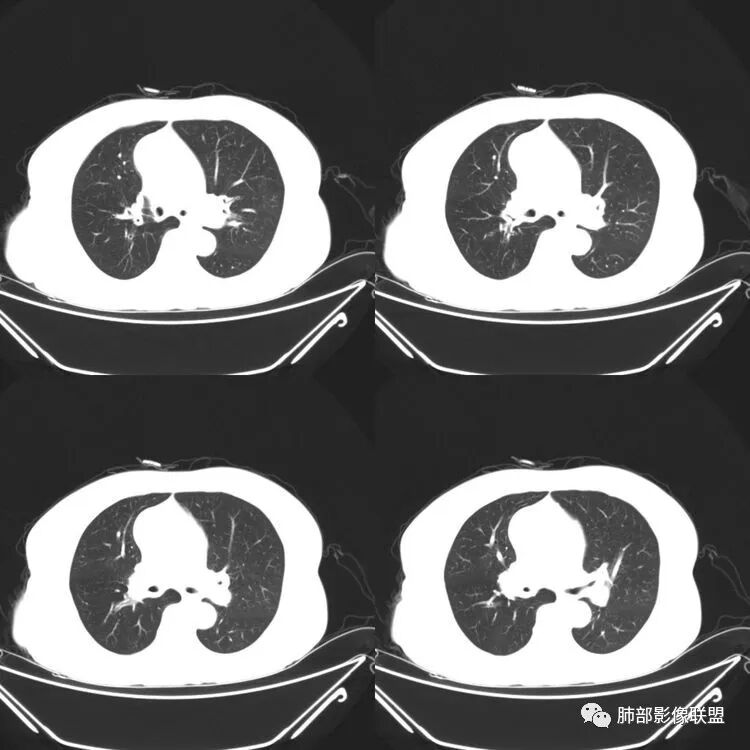

患者,女,64岁,反复咳嗽、咳痰、胸闷10年,加重2周患者10余年来每当受凉感冒出现咳嗽、咳痰、胸闷,有时痰中带血,输液治疗(具体不详)可好转。既往有声带肥厚手术病史。CT示气管、主支气管及分支支气管管壁弥漫性增厚累及膜部,局部伴钙化,管腔狭窄,考虑淀粉样变性

患者,女,64岁,反复咳嗽、咳痰、胸闷10年,加重2周。气管支气管及两肺下叶 支气管弥漫性的环状增厚,管腔扩张,管腔感觉比较松弛。第一感觉,气管支气管淀粉样变。鉴别诊断,1、支气管内膜结核,肺内散在一些支气管的播散病灶,粟粒结节为主,形态比较单一。2、复发性的多软骨炎,就得了解一下其他部位,有没有多个部位的软骨炎。这个病人右侧胸廓缩小,升主动脉明显的扩张,其横径明显的超过了降主动脉。

征象很明确

弥漫支气管壁增厚,膜部受累

声带肥厚——受累

隐约见钙化

南边:肺部有肺气肿支气管腔狭窄淀粉样变性?复发性多软骨炎?血管炎?慢支?结核?曲霉菌?南边:一般还是淀粉样变性与复发性多软骨炎鉴别其次就是支气管骨化症,但是骨化下朝上,且壁结节状钙化明显,本例不太支持。至于结核、曲霉菌?1.结核,一般不会这么广泛,支气管壁狭窄后扩张2.曲霉菌可以这么广泛,但是支气管壁管腔扩张,而且附近脂肪间隙有炎性反应,不太支持;3.血管炎,一般合并肺内有病灶,但是声带受累,放待排;4.软骨炎一般全身受累,例如耳廓等;而且膜部不受累,不太支持;倾向于淀粉样变性;淀粉分很多型,气管支气管是最常见的。尘缘:影像上生理性钙化与支气管骨化无法区别,镜检也不好鉴别,需要依赖活检,看粘膜中是否合并炎性改变(淋巴细胞,组织细胞等炎性细胞侵润)来鉴别Coke with ice:经常看到的这种是老年性肺改变,又称年龄相关肺改变。气管和支气管弥漫性软骨钙化,常见老年女性。尘缘:支气管骨化症很罕见的,所以绝大多数还是生理性钙化。对于老年人,无临床症状的钙化,还是基本上都是生理性钙化,无临床意义。大雄:如果管壁钙化伴明显增厚 影像还是提示一下建议支气管镜稳妥些

三、影像表现

1.气管支气管型

①气管支气管壁增厚,形成粘膜下斑块与结节

②管腔广泛狭窄、闭塞

③管壁钙化

④膜部受累(具有重要鉴别意义)